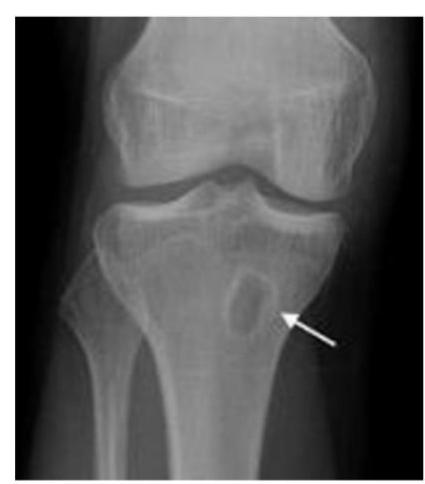

A teenager with acute onset of pain in the right hip during a run. He sustained the injury seen in the x-rays with a white arrow. This injury usually occurs due to a forceful eccentric contraction of which of the following muscles?

- C. Rectus femoris

- Sartorius

Pelvic Anatomy

Which of the following muscles is attached to the structure pointed by the arrow?

- C. Sartorius

Note: Arrow was pointing at ASIS (Anterior Superior Iliac Spine)